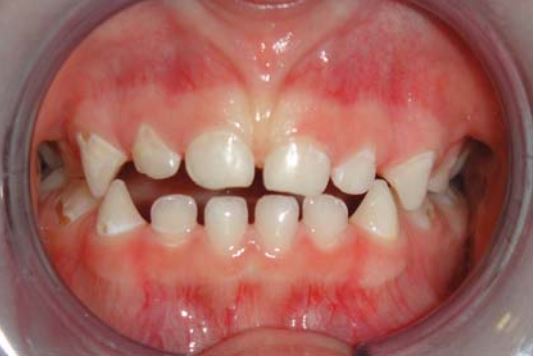

Răng mọc lên chưa hoàn toàn

Trám sealant cho những răng này thường khó vì khó cách li, do đó khuyến cáo trám bằng các vật liệu ưa nước như GIC hoặc sealant GIC (Vitrebond). Răng được theo dõi liên tục cho đến khi mọc lên hoàn toàn, lúc đó sẽ thay lớp GIC bằng sealant.

Nên thông báo cho bố mẹ trẻ về những yếu tố ảnh hưởng đến sự lưu giữ miếng trám như: vệ sinh răng miệng, men răng thiểu sản, nghiến răng, ăn thức ăn cứng và mức độ nhạy cảm với sâu răng.